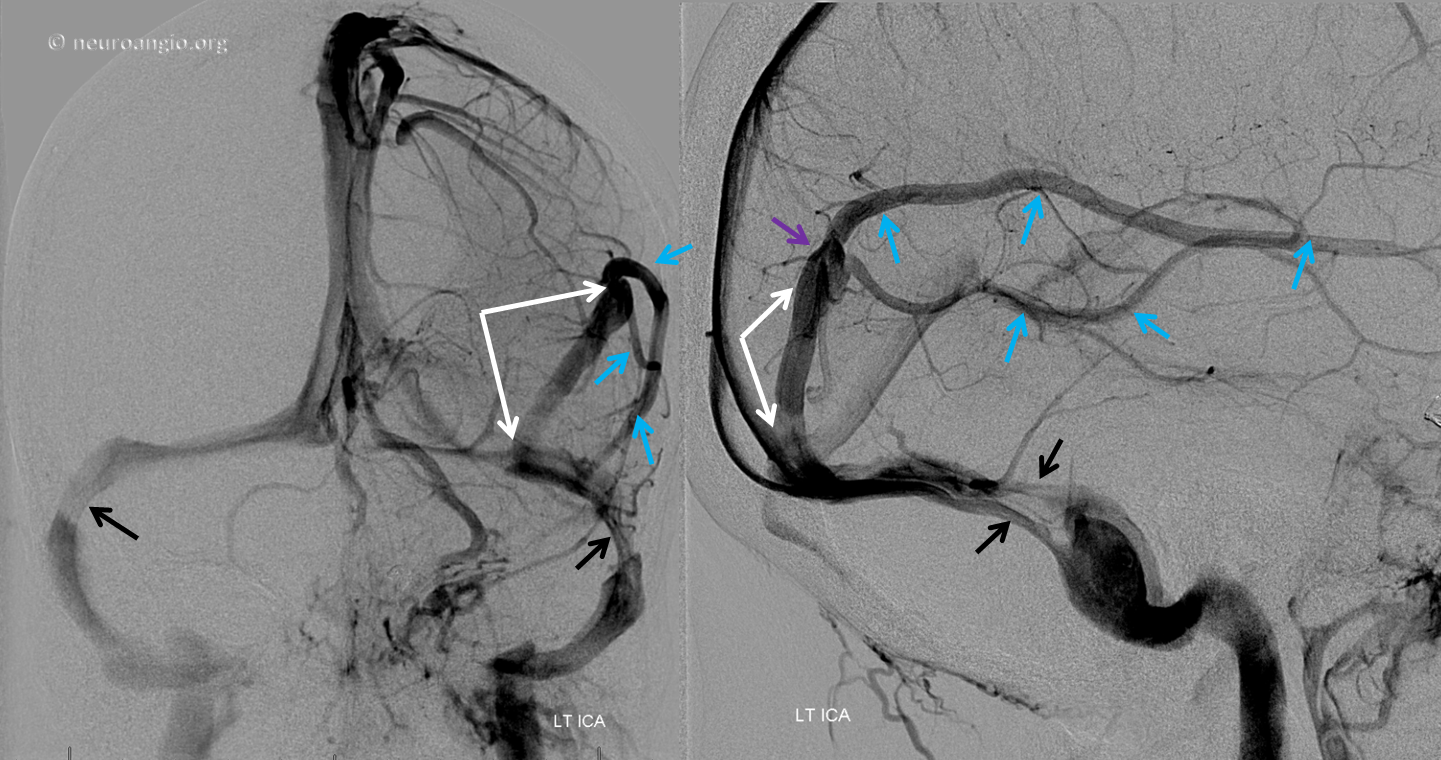

Below is an example of a parieto-occipital dural sinus (white) which collects a somewhat peculiar duo of surface veins (light blue). The transition from cortical vein to dural sinus is marked by the purple arrow. It is typical to see dural sinuses associated with larger, more dominant surface veins, probably because dural sinus is not a favored embryologic structure, and in order for it to persist the flow demand must be somewhat high. Notice also bilateral transverse/sigmoid sinus stenoses in this patient with pulsatile tinnitus and intracranial hypertension.

MRI of the same patient shows the characteristic rounded appearance of the cortical vein (light blue arrows), located just medial / deep to the dura (brown arrows), as distinct from the flattened, oval look of the dural sinus (white arrow). The post-contrast high-resolution T1-weighted images are the best way to look for dural sinuses like this one on non-invasive imaging